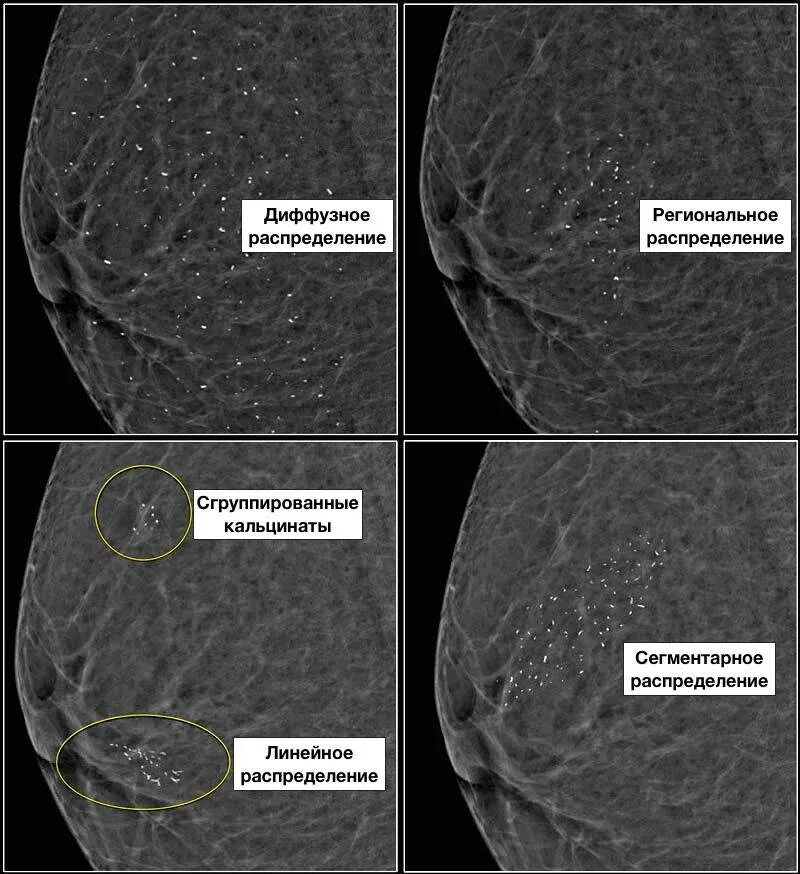

Сгруппированные микрокальцинаты